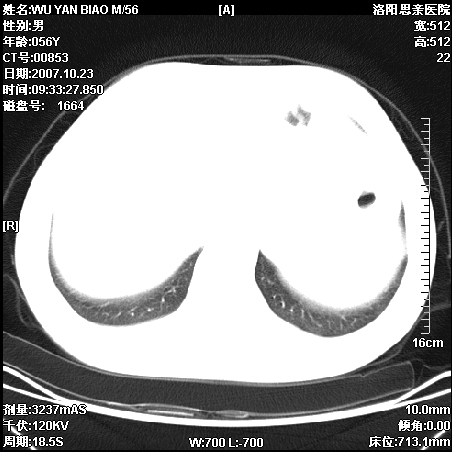

标题: CT10160:M56Y,体检发现,病人无不适,病人随访中 [打印本页]

标题: CT10160:M56Y,体检发现,病人无不适,病人随访中

后上纵隔占位,与肺交界清,宽基底附着脊柱,密度均匀,局部骨质无明确改变.

考虑;神经源性肿瘤,---起源交感n链?,不除外肠源性囊肿.

后纵隔神经原性肿瘤可能性大,孤立性胸膜间皮瘤待排.

支持后纵隔神经源性肿瘤!鉴别胸腔纤维瘤。